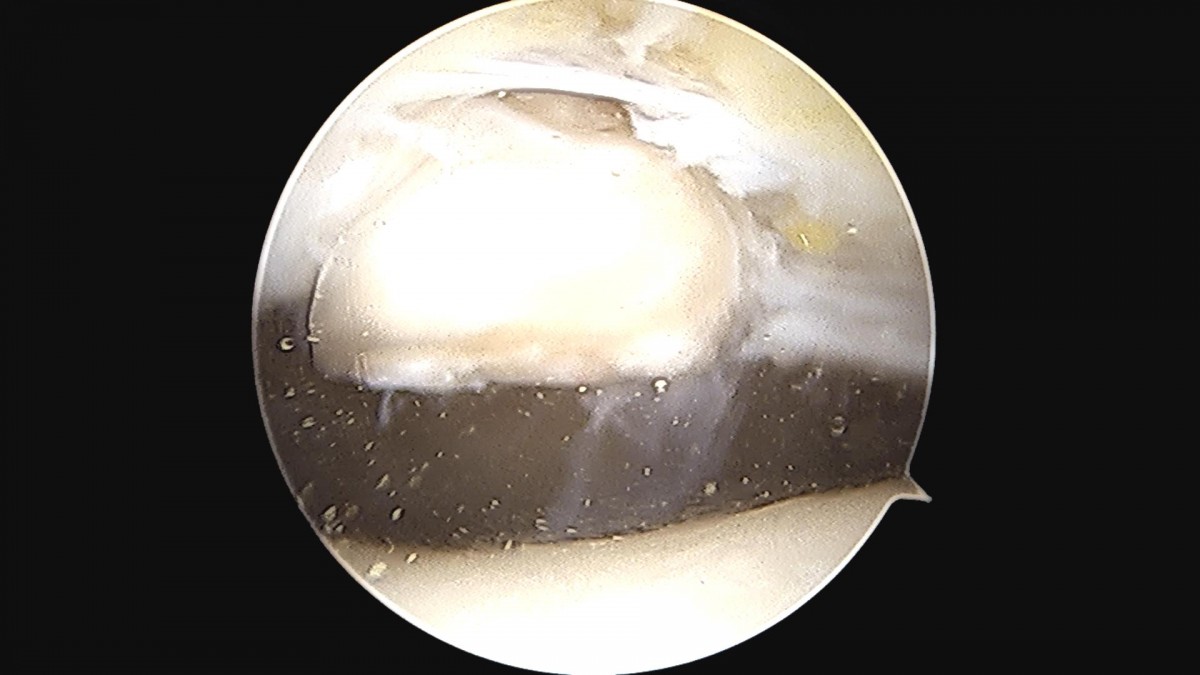

배우한 원장님 발목 활막 절제술 및 골극제거술, 미세천공술 김민O 환자

8b0c7da4bf0a0c139df98fc62b3e688e_1702369254_8089.jpg

8b0c7da4bf0a0c139df98fc62b3e688e_1702369255_1221.jpg

8b0c7da4bf0a0c139df98fc62b3e688e_1702369255_4471.jpg

8b0c7da4bf0a0c139df98fc62b3e688e_1702369255_7659.jpg

8b0c7da4bf0a0c139df98fc62b3e688e_1702369256_1089.jpg

8b0c7da4bf0a0c139df98fc62b3e688e_1702369256_4656.jpg

8b0c7da4bf0a0c139df98fc62b3e688e_1702369256_8087.jpg

8b0c7da4bf0a0c139df98fc62b3e688e_1702369257_1618.jpg

8b0c7da4bf0a0c139df98fc62b3e688e_1702369257_5079.jpg

8b0c7da4bf0a0c139df98fc62b3e688e_1702369257_8534.jpg